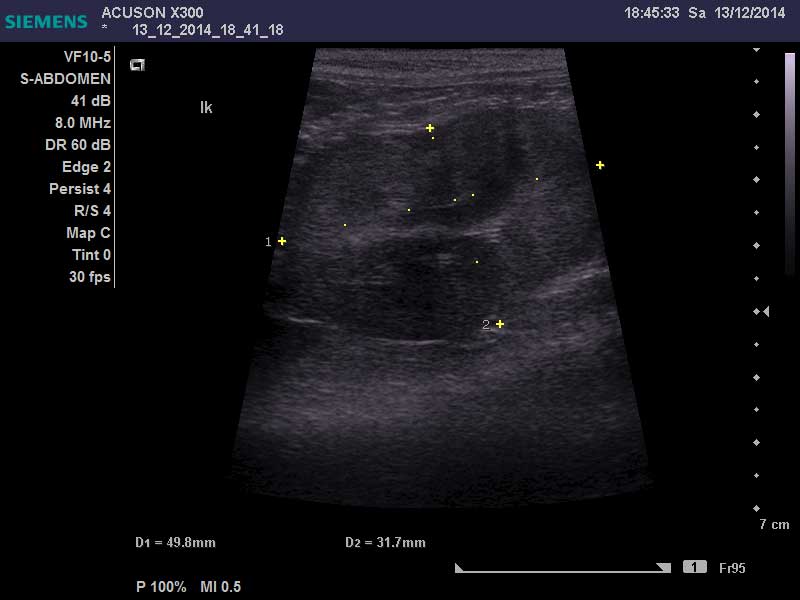

回生在醫院一共住了16天調養身體,X光及超音波顯示她的2顆腎都長了腫瘤也變形,醫生也無法進行手術、貧血的狀況也一直沒有良好的改善...醫生建議秀雲姐帶回去做安寧照護,回生已於12/27回到喵喵茶,秀雲姐這幾天也有持續帶回生回診治療,希望回生可以好好渡過每一天!!!